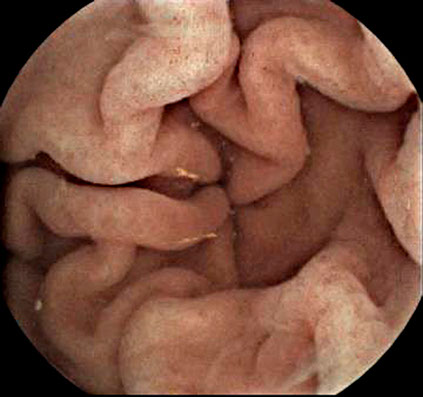

Case Gallery